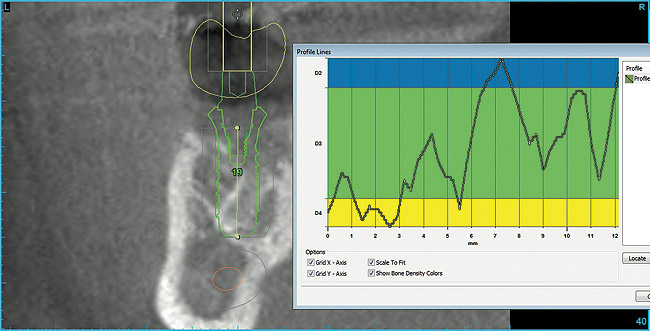

Not only does guided surgery result in safe and accurate implant placement, but by predetermining the path of implant insertion, the bone density of the osseous receptor site can be predetermined, which may affect the surgical procedure. In softer bone, clinicians will often under-prepare the osteotomy dimensions to increase the likelihood of achieving primary implant stabilization. Using Hounsfield units to estimate bone density, the surgeon can begin a surgical procedure with increased knowledge of the qualitative bone density prior to starting osteotomy preparation. Misch10 classified bone density by radiodensity numerical values to assist in approaching surgical implant placements. The bone density of each millimeter of osteotomy depth can be determined with planning software, giving the surgeon greater insight to the proposed implant bed (Figure 19). Turkyilmaz and McGlumphy11 found a clinical correlation between Hounsfield units measured on CT scans of proposed implant locations, insertion torque, and implant stability (ISQ). The radiodensity of sites of failed implants was consistently lower than those sites of successful implants. The authors concluded that a non-invasive method, such as CT scanning, may be used prior to implant surgery, and may allow clinicians to plan on modifying their approach before starting active therapy. Most implant planning software is capable of measuring bone density via Hounsfield units, which makes the realization of drill resistance prior to surgery a possibility for clinicians today.

Figure  19  Hounsfield units of each millimeter of proposed osteotomy calculated via planning software.

Figure 19